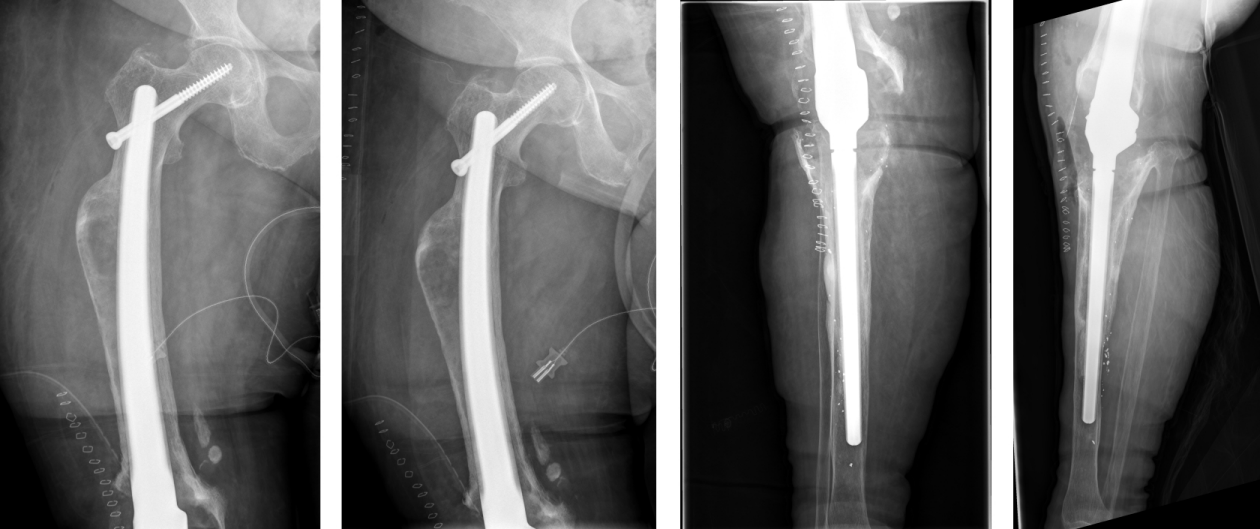

Surgery was performed in supine position allowing intraoperative two-plane imaging of the right lower limb (Figure 6 [Fig. 6]). Using the anterior median approach of the knee joint, the cement spacer and the intramedullary carbon nails were removed. There was no macroscopic evidence of infection in the entire surgical area. Nevertheless, swabs were taken from the intra-articular area as well as from the medullary spaces and histopathological specimens from the intra-articular connective tissue. After meticulous debridement and sufficient lavage, the tibial nail was inserted. Afterwards, we performed a lateral approach to the right major trochanter. We introduced an awl under imaging control (Figure 7 [Fig. 7], Figure 8 [Fig. 8]). The sclerosis zone was opened both proximally and distally (Figure 7 [Fig. 7], Figure 8 [Fig. 8]). A Kirschner wire was then inserted into the femoral neck area to mark the entry of the femoral neck screw. The femoral nail was implanted, taking into account the rotation and position of the femoral neck screw. After the Kirschner wire had been removed in the area of the femoral neck, the femoral nail could be driven in further and the femoral neck screw could be properly inserted under imaging control (Figure 7 [Fig. 7], Figure 8 [Fig. 8]).

Figure 7: Intraoperative steps (see text)

Lateral approach to the thigh, exposure of the femoral shaft and the fracture, exact measurements according to preoperative planning to identify the planned level of resection. Exposure of intramedullary femoral stems, the diaphyseal femur the implants were cemented and additionally secured circularly with screws to the two stem parts after setting the correct rotation. Then, the two parts were connected using the screws provided.

Figure 8: Intraoperative radiographs